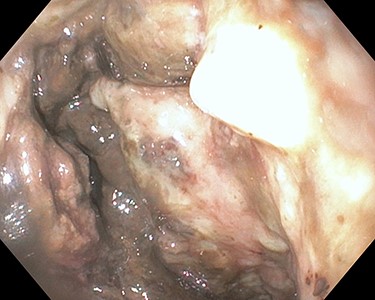

resuscitated with 4 units of packed red blood cell. Upper endoscopy was suspicious for a large paraesophageal hiatal hernia with necrotic mucosa and adherent clot versus penetrating proximal gastric ulcer (Fig. 1) as a possible source of upper gastrointestinal bleeding. Computed tomography showed a largeheterogeneous mass occupying the spleen with air suspicious for splenic abscess versus large mass perforating stomach and colon (Fig. 2). She underwent exploratory laparotomy, en bloc partial gastrectomy with splenectomy and partial left colon resection with colostomy. GSF was observed with the greater curvature of the stomach and a splenocolonic fistula was observed with the splenic flexure of the colon (Fig. 3). There was tumor

Esophagogastroduodenoscopy showing necrotic mucosa over the greater curvature of the stomach on retroflex view